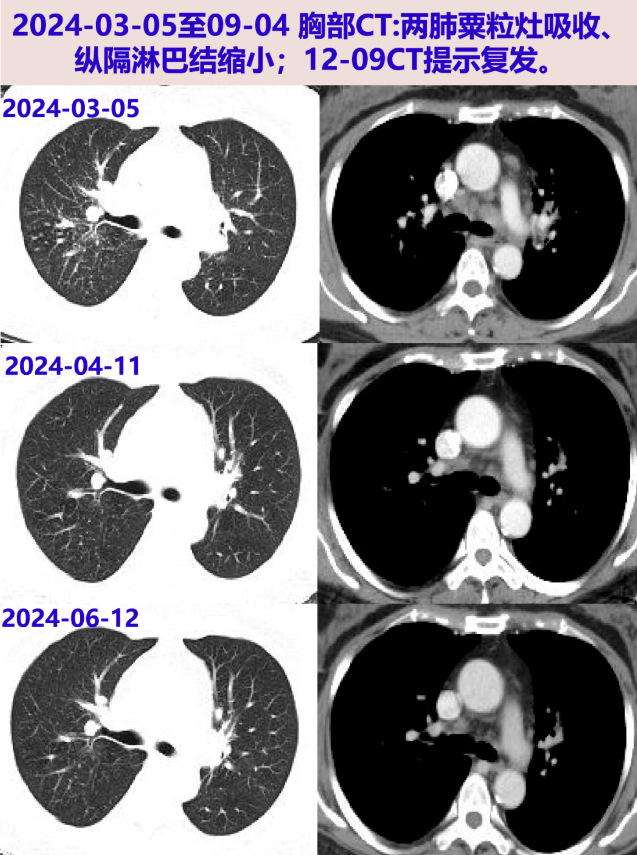

2024-04-11 胸部CT:两肺炎症、纵隔淋巴结肿大较前片明显好转。继续甲泼尼龙20mg qd ×1周(共2周),后续减量方案:16mg qd×2周、14mg qd×2周、12mg qd×2周。

2024-06-12 淋巴结、灌洗液分枝杆菌培养(2024-03-07采样):阴性。胸部CT:两肺炎症病灶明显吸收,纵隔淋巴结明显缩小,较04-11相仿;复查炎症标志物、ACE阴性。当前甲泼尼龙10mg qd,后续每2周减量2mg至停药。

2024-08-26 停用甲泼尼龙。09-04胸部增强CT:两肺门及纵隔多发小及增大淋巴结,较06-12片部分稍大。继续停药。

2024-12-09 胸部CT:纵隔及肺门多发淋巴结肿大,两肺多发病变,均较09-04片进展;ACE阴性。考虑结节病复发,再次启动糖皮质激素治疗,方案:甲泼尼龙32mg qd×1周、28mg qd×2周、24mg qd维持。